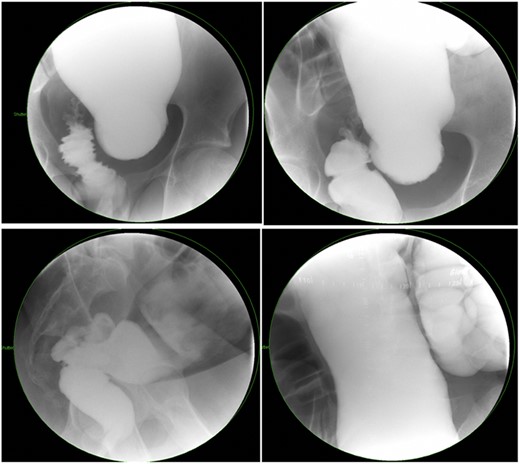

There is a subset of patients in whom primary transanal pull-through in those >2 years of age at the time of surgery is possible. While a previous case series reported that 18.8% of their late-diagnosed HD patients underwent transanal primary pull-through, these authors did not describe outcomes or reasons for choosing the operative approach [7]. In case series, the characteristics of patients who were able to undergo primary transanal-only pull-through include overall earlier age (2–6 years) vs. those diagnosed later. On contrast enema, they exhibited a limited degree of megacolon (Figs 1 and 2). Proximal colonic dilation was absent in all four patients that we felt were good candidates for a transanal-only approach. However, proximal colonic dilation (proximal of the sigmoid) was visualized in 15 patients, and therefore, a transanal-only approach was not offered. The ability to identify a clear transition zone low in the rectosigmoid was also observed in each patient. Finally, the ability to empty the colon preoperatively whether through laxatives or rectal irrigations was also present.

Representative contrast enema study. Note the lack of dilated proximal colon and defined transition zone in the low rectosigmoid colon. (Candidate for transanal only).